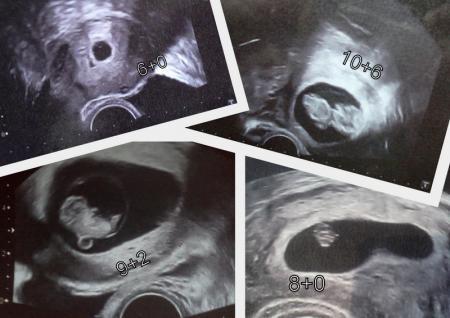

Hallo.Ich habe gerade mal mein letztes Ultraschallbild abfotografiert,weil ich ja noch gar kein Bild gezeigt habe.Da war ich 9+4 wo ich das letzte mal beim Fa war. Ich hab dann mal die Bilder von den anderen mit meinem verglichen und meins sieht eher wie eine kleine Bohne aus.Und bei den anderen wie Gummibärchen.Aber vielleicht weil meins von der Seite ist,sieht man aber ganz gut glaub ich.Obwohl meine Fa nicht das neueste Ultraschallgerät hat. Lg ana mit Bauchbohne

Bild zu Meine Bauchbohne - Forum für September - Mamis